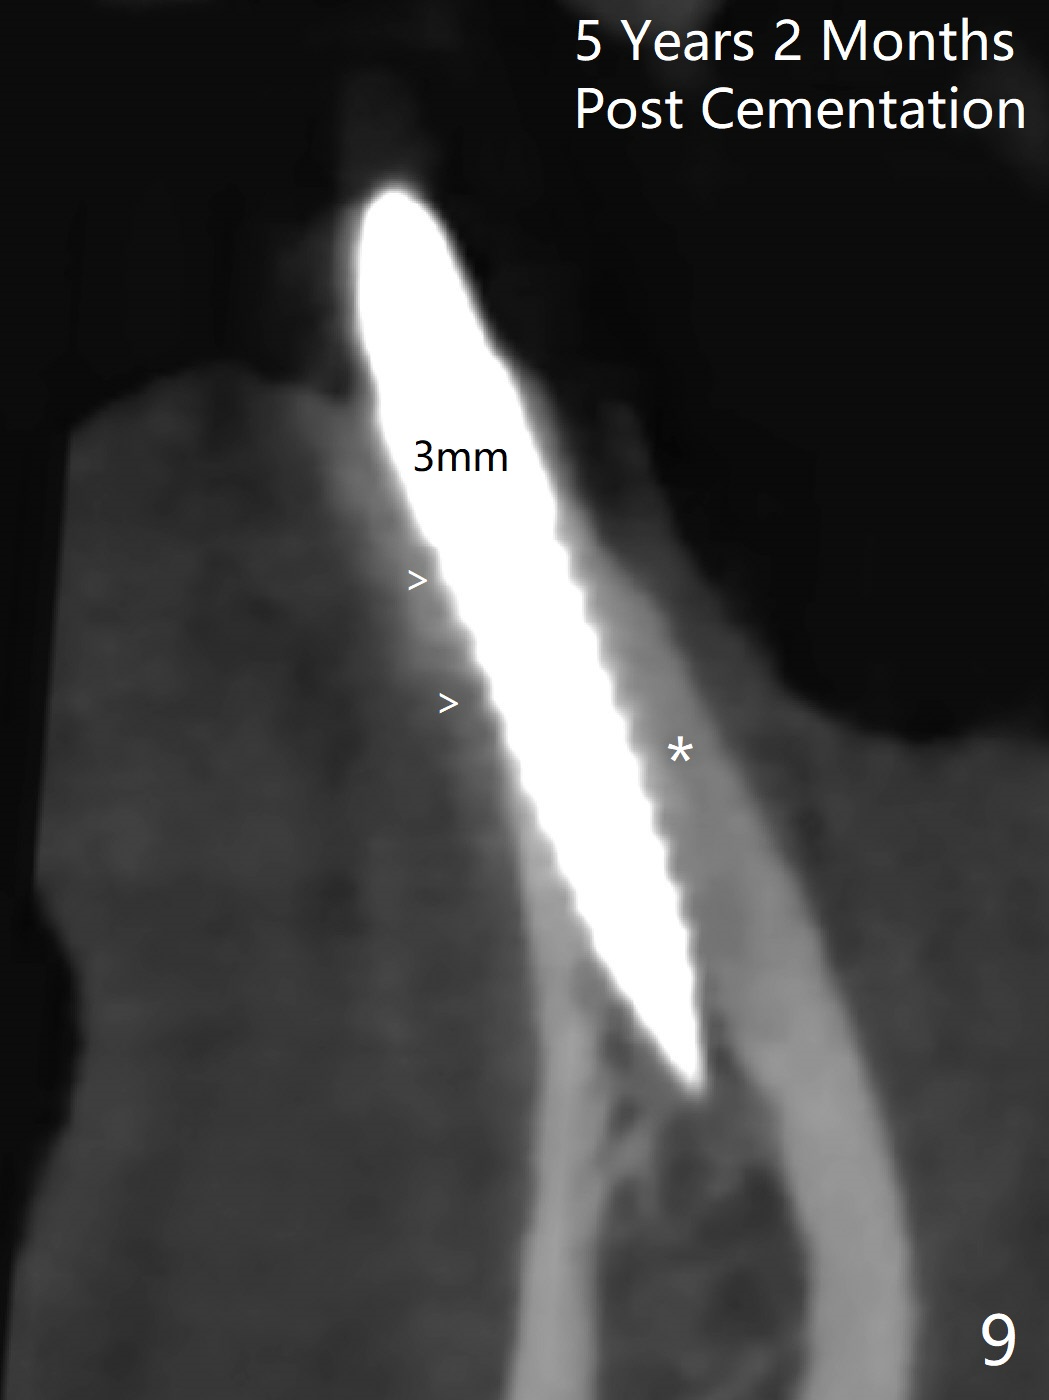

After removing #23-26 FPD and the 3x14 mm 1-piece implant at #26 (Fig.1,2 *), a new osteotomy is initiated in the narrow ridge (after ridge top reduction) approximately at #25 (Fig.2 <). Following placement a 2x10(4) mm implant at #25 (Fig.3-5) and Osteogen plug in the osteotomy at #26, Vanilla graft is placed around the implant, especially buccal. Periodontal dressing is applied after suturing. The buccal and lingual flaps are erythermatous and edematous without pain 8 days postop (Fig.6). The wound seems to be healing 2 weeks postop (Fig.7), no sign of osteonecrosis. With placement of a 2 mm implant at #25 (Fig.8 (>: bone graft buccally)), the buccal plate remains normal in thickness. When a 3 mm implant is placed at #23 (Fig.9), approximately 4 threads appear to be exposed (between arrowheads), partially due to the thick lingual plate (*).